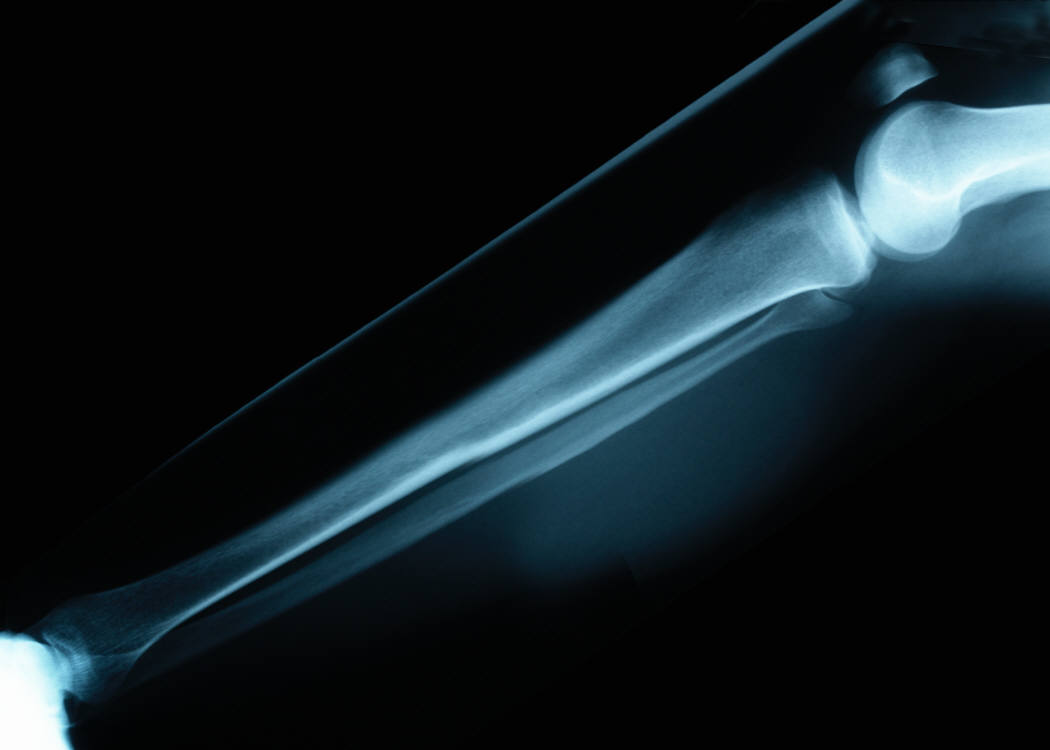

Beginning with shin splits, which are often triggered by abrupt changes in activity, there are signs and symptoms for which to look. The first thing you’ll notice, obviously, is the pain. It’s a dull ache of sorts and very nagging. You may feel this ache in two different parts of the leg, and not always in both. The first location is just to the inside of the shin bone, more toward the back of the leg. The next spot is to the outside of the shin bone, more on top of the leg. This dull ache is actually inflammation of the connective tissue covering the bone. Don’t worry, no surgery is required to fix this type of injury!